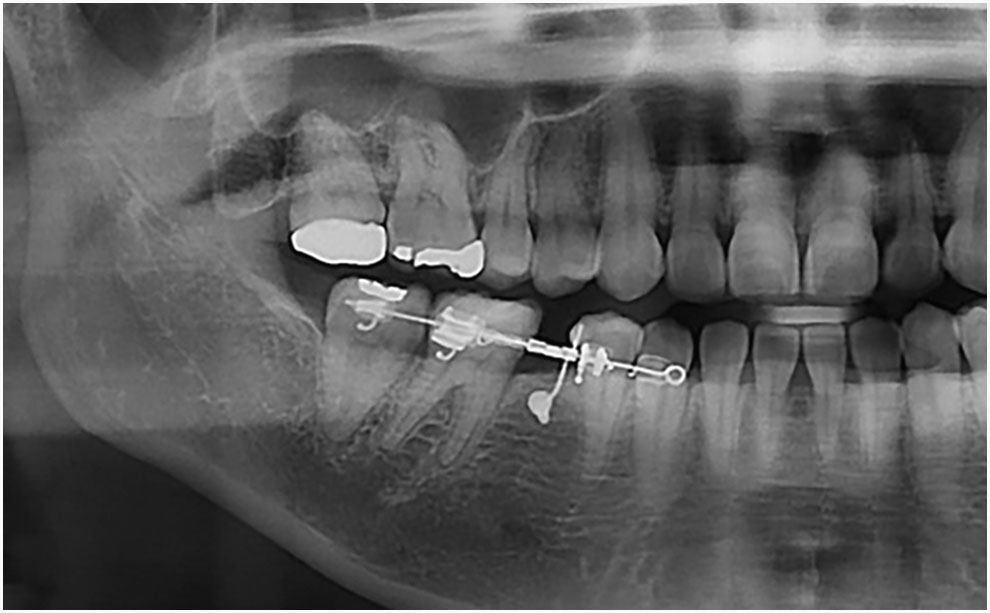

예를 들어, 어금니를 충치로 인해 잃었음에도 적절한 시기에 보철 치료나 임플란트를 하지 않고 방치한 사례가 종종 있습니다.

이러한 상황에서는 빈 공간으로 인접한 치아들이 기울어지거나, 반대쪽 치아가 점점 내려와 임플란트를 심을 공간이 부족해질 수 있습니다.

이럴 경우, 임플란트교정 을 통해 기울어진 치아를 제자리로 되돌리고 적절한 공간을 만든 뒤 임플란트를 심어야 효과적인 치료가 가능합니다.

- 오랜 기간 치아를 발치한 채로 방치한 경우

교정 치료의 순서 는 기울어진 치아를 올바르게 정렬하거나 임플란트를 심을 공간을 우선 만듭니다.